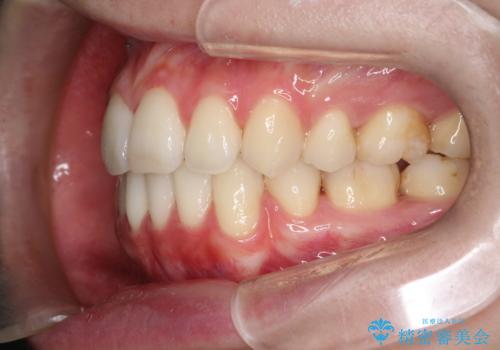

口元が出てるの気になる ハーフリンガルによる抜歯矯正での横顔改善

抜歯矯正により、前歯をしっかり下げることで口元がすっきりしました。